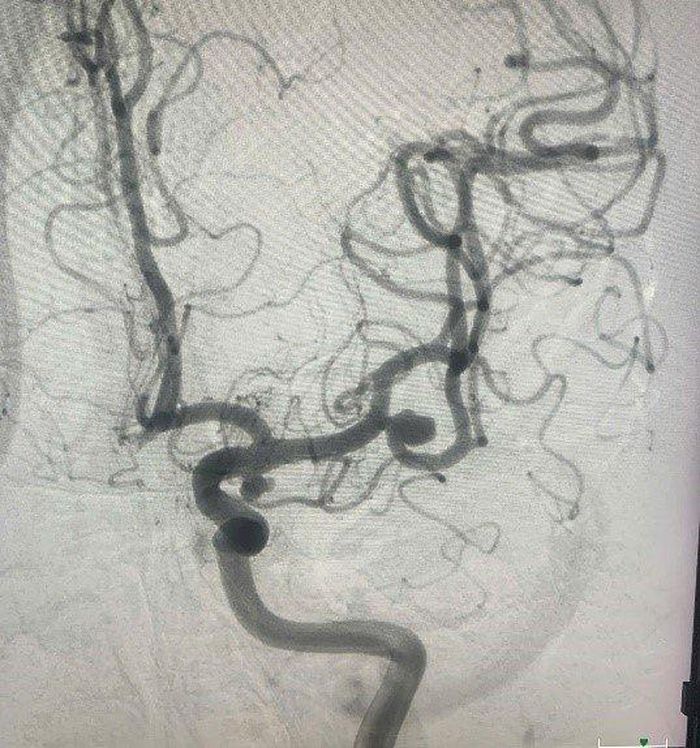

Hình ảnh phình động mạch não.

TS.BS Lương Tuấn Anh, Khoa Chẩn đoán và Can thiệp Tim mạch, Bệnh viện TWQĐ 108 cho biết, bệnh viện vừa tiếp nhận bệnh nhân P.V.D 58 tuổi (Hà Nội) vào Khoa Chẩn đoán và Can thiệp Tim mạch - Bệnh viện TWQĐ 108 vì đau đầu âm ỉ suốt 2 tuần, uống thuốc không hết đau. Kết quả chụp CT cho thấy bệnh nhân bị phình động mạch não, có khả năng vỡ cao nên bác sĩ cho nhập viện, chờ can thiệp nút túi phồng bằng lò xo kim loại.

Can thiệp phồng động mạch não có nhiều phương pháp, bệnh nhân P.V.D đã được chọn kỹ thuật nút túi phồng bằng lò xo kim loại. Quá trình điều trị thuận lợi, bệnh nhân được ra viện sau 24h, trở lại cuộc sống bình thường.